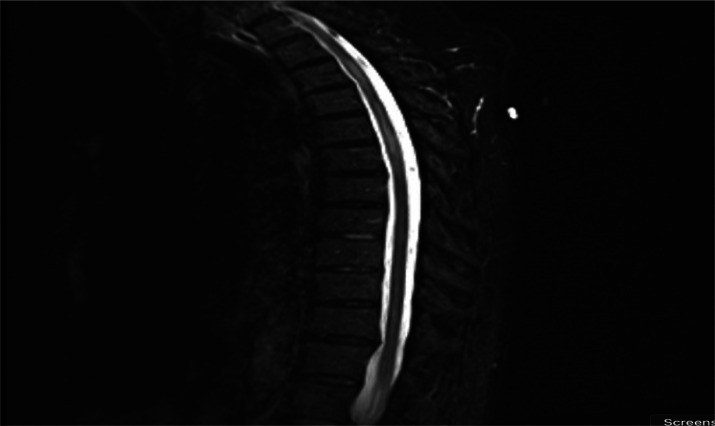

Abstract Image